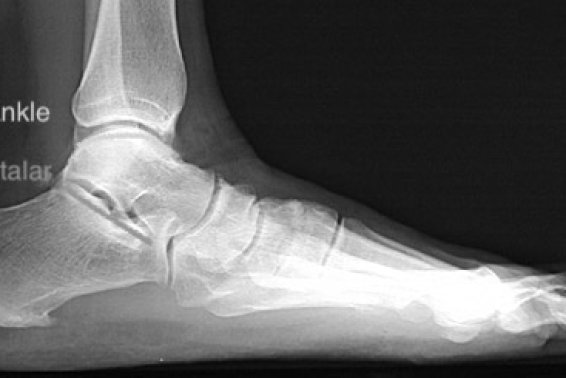

What scan do I need for my painful foot?

Within the domain of foot and ankle treatments, accurate diagnosis plays a crucial role in ensuring effective patient care. Various imaging ...